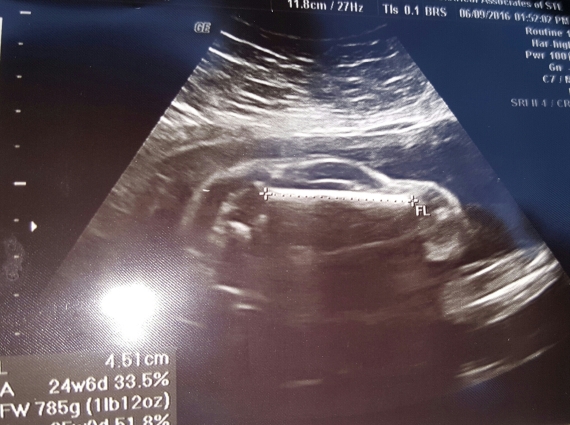

لو كانت فكرة الحصول على أطفال تبدو أسعد حدث للوالدين أو أنها أحياناً قد تدفع بعض الأزواج للجنون، تخيلي حالك إذاً كنت سوف تصبحين أمّاً لسيارةِ مرسيدس أو أنّكَ ستصبحُ أباً لسيارةِ كاديلاك أو عماً لشيطان.

هكذا كان شعور سيدة حامل أظهرت صورة الموجات فوق الصوتية بالفعل طفلها بشكل يشبه السيارة في رحمها، ما ترك المشاهدين في حالة ذهولٍ متسائلين عن كيف يمكن لطفلٍ أن يشبه سيارةً؟، وفقا لتقريرٍ لصحيفة ذي صن البريطانية.

وتم نَشر هذه الصورة العجيبة على موقع ريديت عن طريق Brewhaus3223 الذي أرفق الصورة العجيبة بعنوان "زوجتي حبلى بسيارة رياضية".

وقد حازت الصورة على آلاف النقاط على ريديت، وشارك المستخدمون بتعليقات مرحة حول الصورة الغريبة.

وتعددت التعليقات على الصورة، فمزح أحدهم قائلا بأن الأم "قضت وقتاً طويلاً أمام فيلم المتحولون (Transformers)". وأضاف آخر "حلٌ مثاليٌّ لأزمة منتصف العمر".